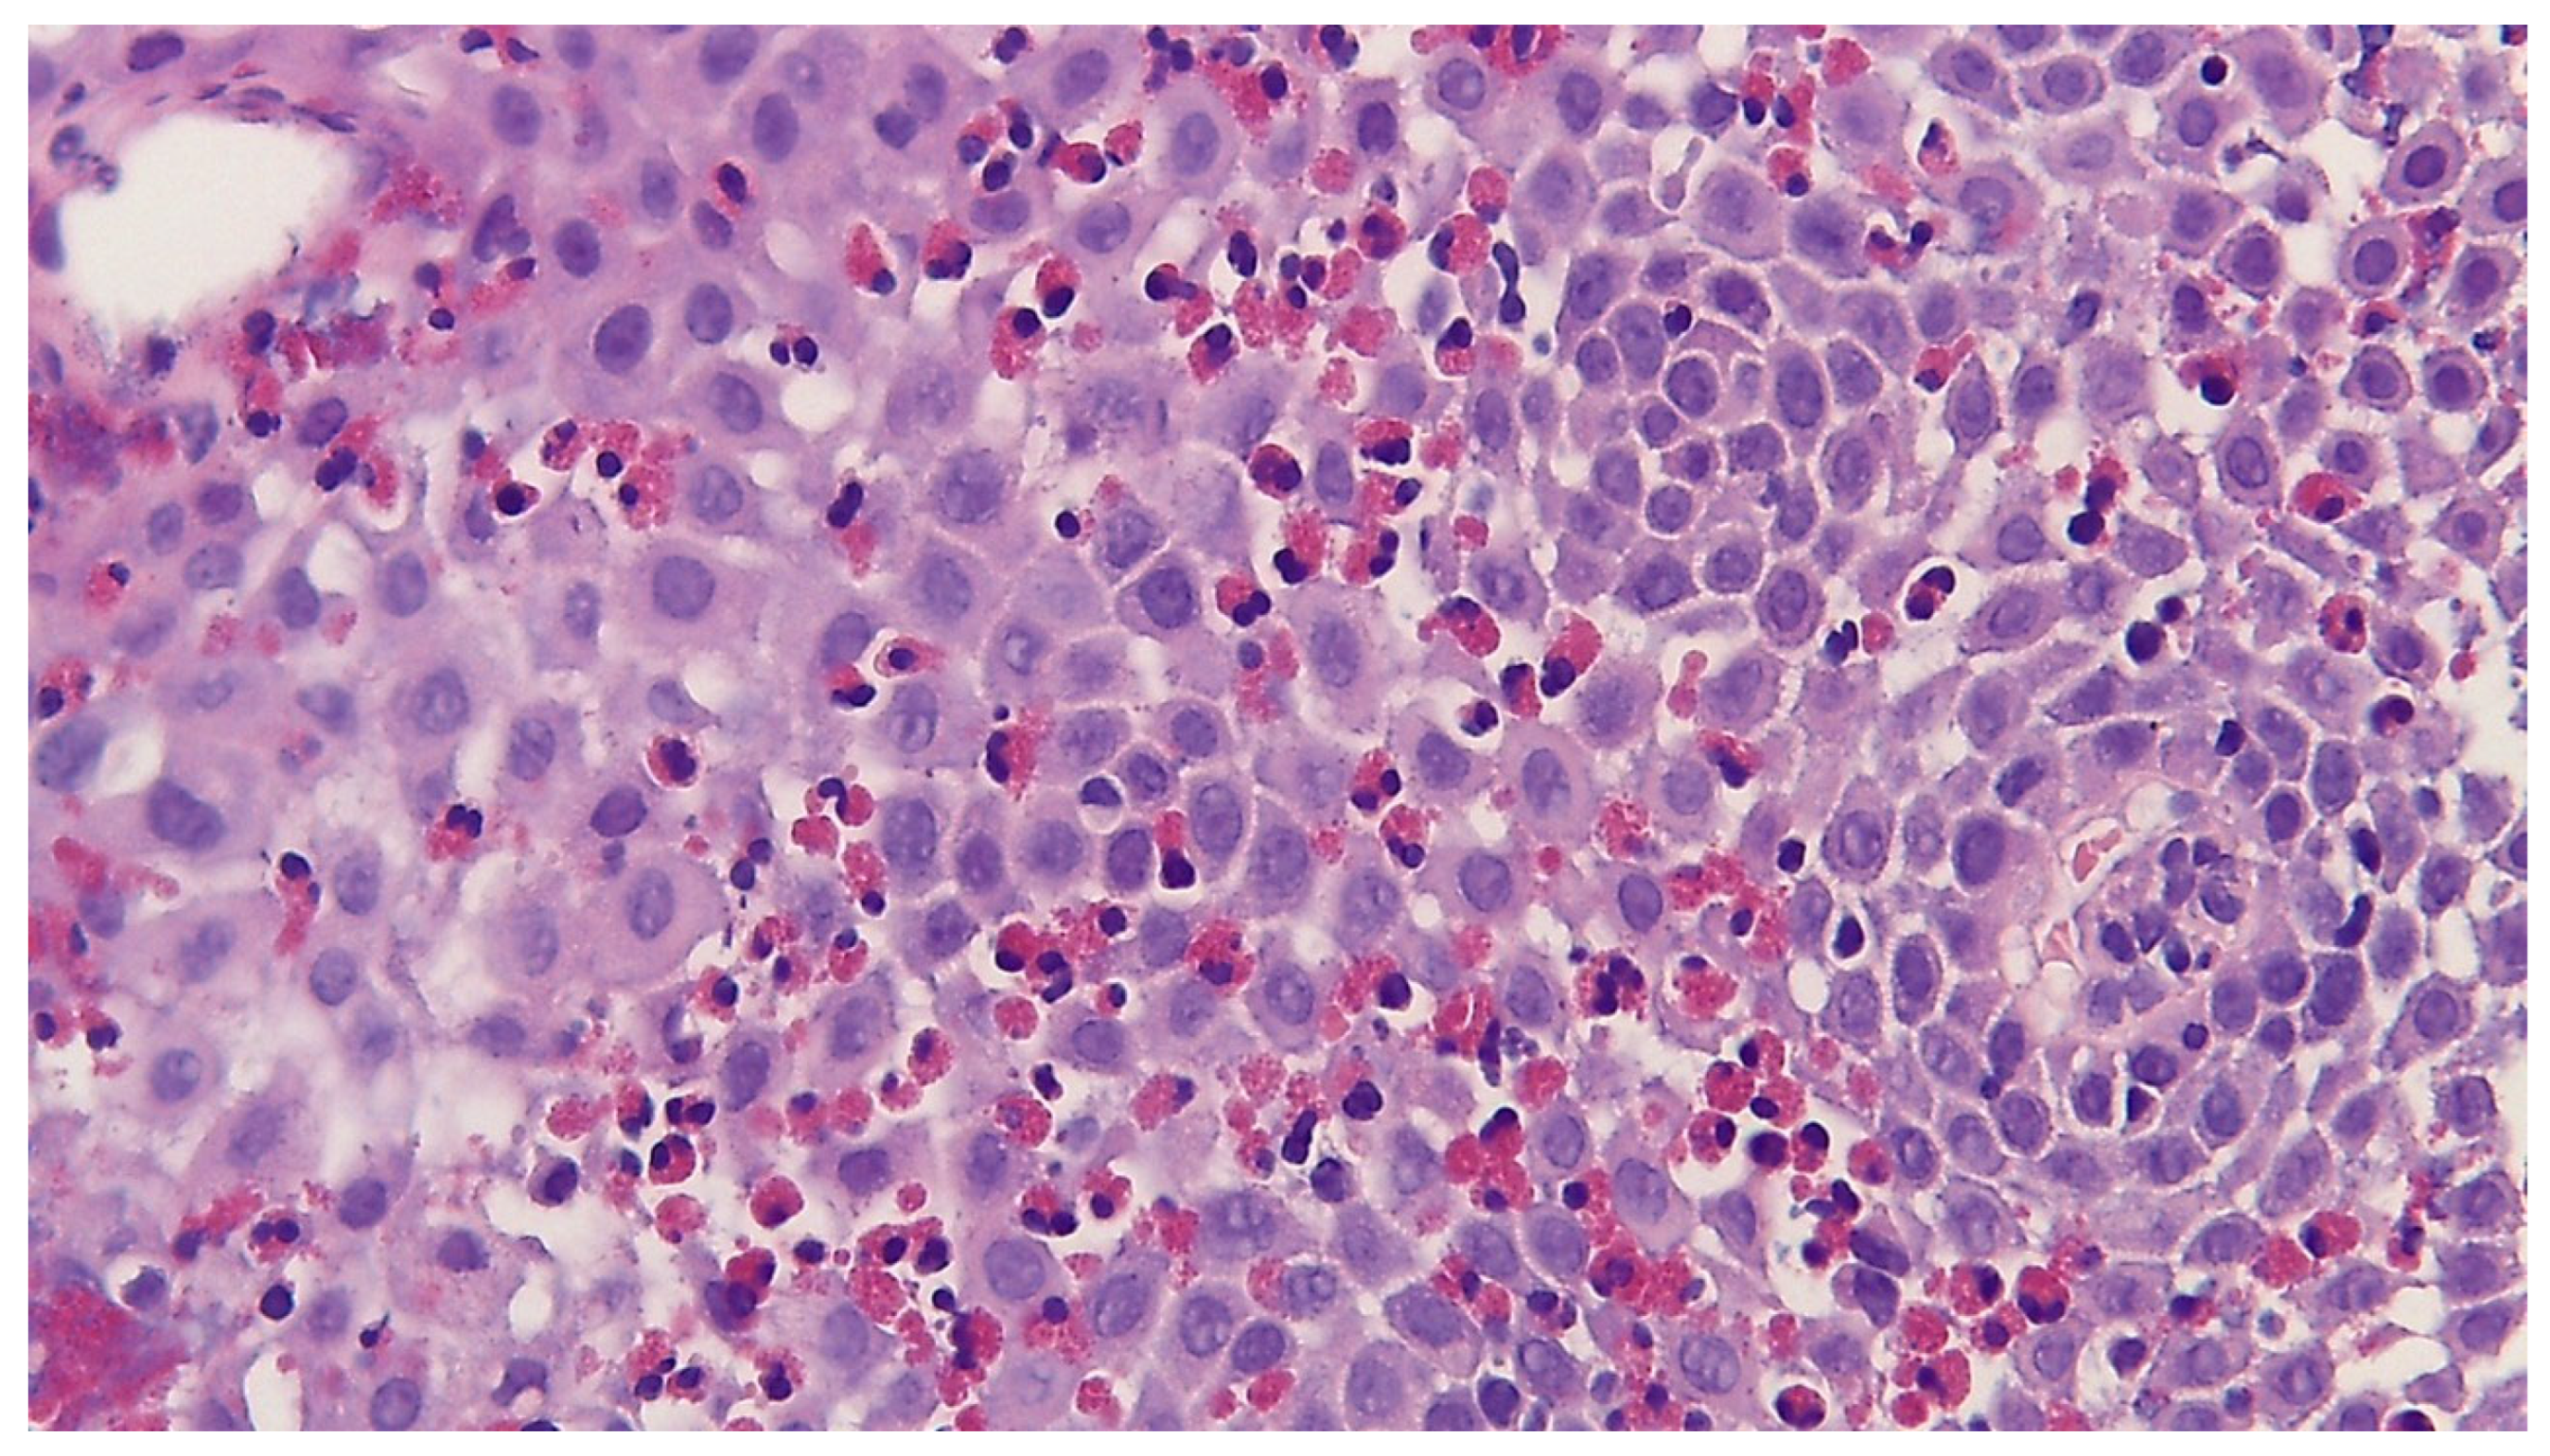

2. Histological Analysis and Diagnostic Criteria